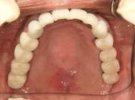

54歳女性

部分義歯がどうしても違和感が強くて、できれば義歯を使わなくてもいいようにしたいとのこと。

下顎はそんなに問題ないですが、上顎は骨の厚みと量、共に乏しく本来はインプラントは不可能です。

あきらめずに、かなり高度な技術ですが骨を増やす手術を併用してなんとか植えることができました。

術前

術後